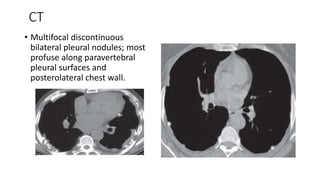

CT

• Multifocal discontinuous

bilateral pleural nodules; most

profuse along paravertebral

pleural surfaces and

posterolateral chest wall.

CT • Multifocal discontinuous bilateralpleural nodules; most profuse along paravertebral pleural surfaces and posterolateral chest wall.